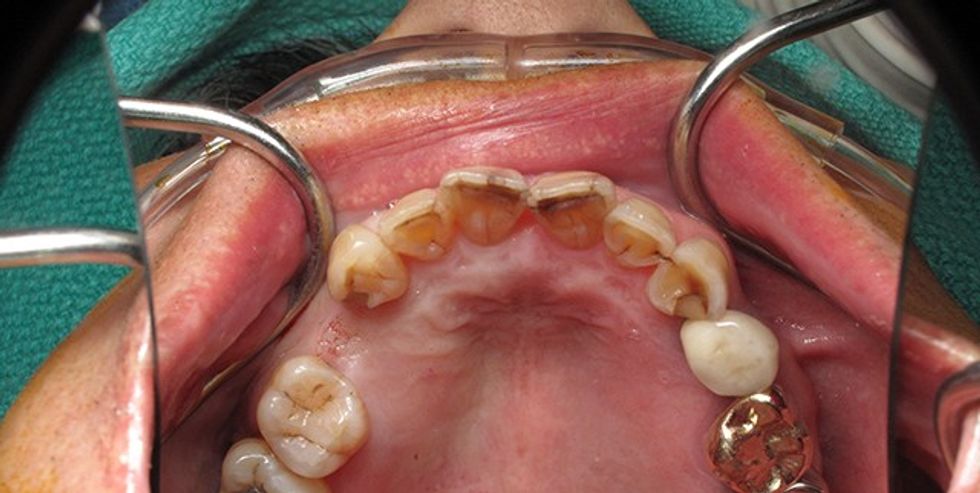

Të sëmurit kanë tendencë të kenë raste më të shpeshta të sëmundjeve parodontale, shkallë më të lartë të humbjes së kockës dhe të infeksionit, dhe shpesh përjetojnë episode akute me aktivitet agresiv të sëmundjeve parodontale, që përfundimisht rezultojnë me humbjen e dhëmbëve. Humbja e dhëmbëve e bën më të vështirë përtypjen dhe tretjen e ushqimit që për të sëmurit nga diabeti mund të ketë ndikim të dëmshëm në aftësinë e të ushqyerit të drejtë dhe mbajtjes nën kontroll të nivelit të sheqerit në gjak.

Sëmundjet parodontale janë infeksione bakteriale të mishit të dhëmbëve (gingivës) dhe aparatit mbështetës të dhëmbit (parodonciumit). Shkaktari kryesor sëmundjes është pllaku bakterial, një shtresë mikrobiale, e ngjitshme dhe e pangjyrë që sajohet në dhëmbë.

Nëse ky pllak nuk largohet çdo ditë me brushë dhe me penj, ai ngjitet fortë për dhëmbë dhe shndërrohet në një substancë të vrazhdë dhe poroze që quhet gur i dhëmbit (kalkulus). Toksinet (produktet helmuese) që prodhohen nga bakteret e pllakut e irritojnë mishin e dhëmbëve (gingivën) duke shkaktuar infeksion.

Shenjat më të shpeshta të sëmundjeve parodontale janë gjakderdhja, ënjtja dhe zhveshja e mishit të dhëmbëve, e më vonë mund të vijë deri te luhatja dhe rema e dhëmbit. Gjatë sëmundjes mund të paraqitet edhe abscesi (qelbi) që për dallim nga shenjat e mësipërme,

përcillen me dhembje të theksuara. Poashtu, nuk mungojnë as duhma dhe shija e keqe në gojë.